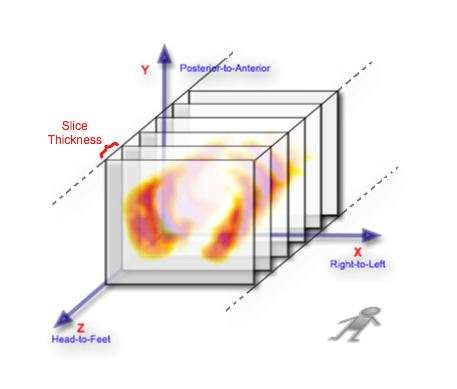

Its helpful, before proceeding, to consider the axial slices, be they SPECT or CT, stacked one behind the other, as illustrated below:

Notice that the figure illustrates each image as a thin slice when the data represents in reality a slice wide enough to fill the gap between it and the next slice, so that the image data can be considered to be a matrix of volume elements - called voxels for short.

A convention applied in medical imaging is to display axial image stacks with the axes oriented as shown in the following figure:

So the left side of an axial scan represents the patient's right side viewed from below, with their anterior surface at the top of the image. A modification of a little ditty by Spike Milligan might help you remember this perspective: